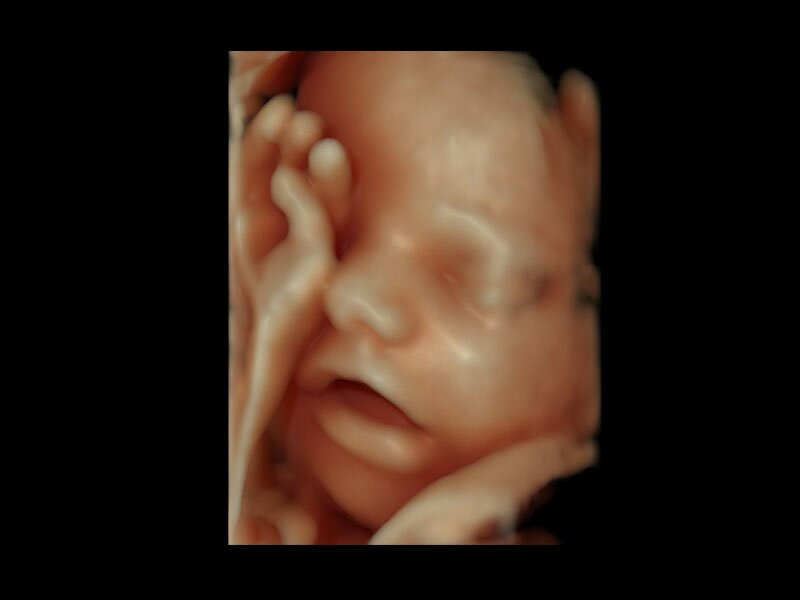

• Программа объемной визуализации плода классический HD-Live + расширенный пакет Hdlive Silhouette и Studio:

• HDlive Flow - перемещаемый источник света, совместимый с визуализацией кровотока в 3D

• HDlive Silhouette - режим "Силуэт" с подчеркиванием границ тканей и объектов, "объем в объеме"

• HDlive Flow Silhouette - режим "Силуэт" с выделением границ полостей сердца и сосудов, совместимый с визуализацией кровотока

• HDlive Studio - три независимых источника освещения с регулировкой интенсивности

• Автоматическое определение плода в режиме 3D (SonoRenderLive) – позволяет значительно экономить время и получать изображение конечностей и лица плода в режимах 3D без артефактов и помех – система автоматически определяет границы конечностей и лица плода и выстраивает объемное изображение

Объемное сканирование Voluson — 3D/4D вашей мечты

Объемное УЗИ на Voluson E10 — это не просто потрясающе красивая картинка, это ценный инструмент получения дополнительной информации при обследовании женщин.

Voluson E10 поддерживает инновационные технологии формирования изображений — HDlive Silhouette и HDlive Flow, которые позволяют увидеть мельчайшие детали. Алгоритм SonoRenderlive упрощает рабочий процесс и дает возможность реконструировать изображение поверхностей, определяя область перехода между тканью и жидкостью.

• HDlive

Инновационная технология визуализации HDlive обеспечивает получение реалистических изображений за счет эффекта объемного зрения, повышая достоверность клинической оценки. Теперь режим HDlive дополняют две новые функции:

• Технология HDlive Silhouette — задает разный уровень прозрачности, помогая выявлять контуры внутренних структур и точнее оценивать состояние плода в первом триместре.